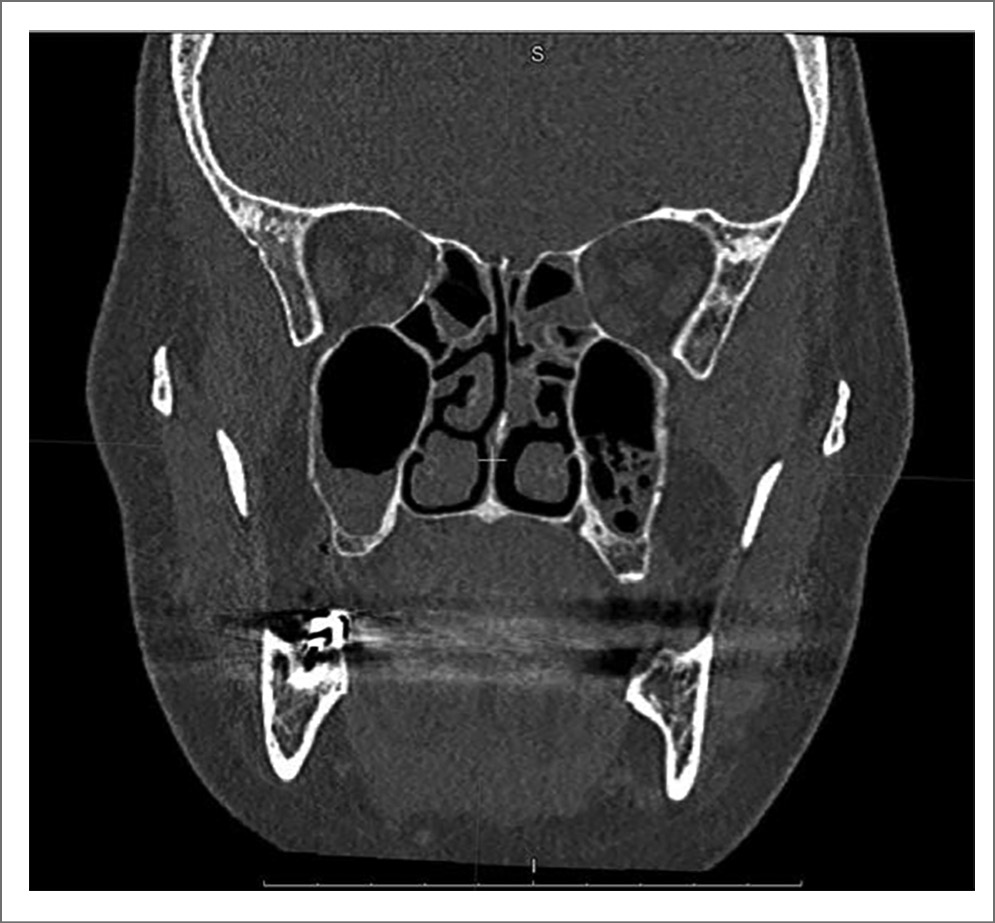

Через 1,5 мес на компьютерной томограмме околоносовых пазух (от 26.05.2022) визуализируется небольшое пристеночное утолщение слизистой оболочки в альвеолярной бухте верхнечелюстных пазух с обеих сторон (рис. 5).

Рис. 5. Компьютерная томограмма околоносовых пазух пациента Л. через 1,5 мес после лечения.